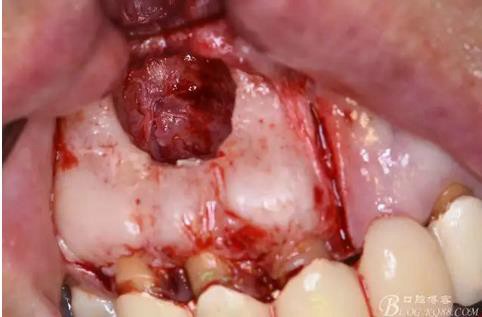

圖4.腭側觀:12根尖正對的腭粘膜隆起、有波動感

圖9.去除唇側薄的骨壁,暴露出囊壁

圖10.剝離囊壁